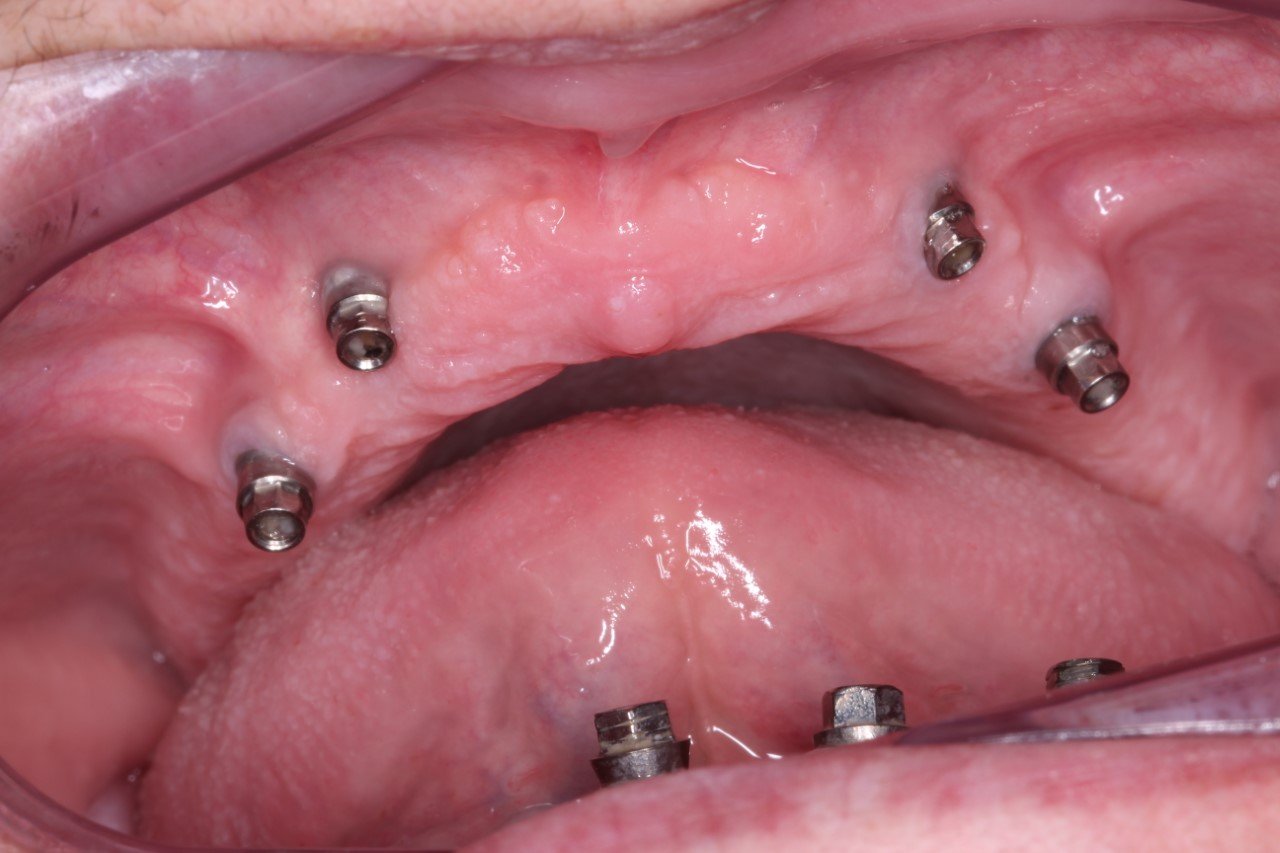

Paciente varón que acude a consulta por pérdida de retención de la prótesis sobre implantes realizada 8 años atrás. Informado del estado de sus implantes necesito colaboración para poder identificar [...]

Buenas tardes, compañeros. Hace algunos meses me llegó este caso y no consigo averiguar que implantes lleva la paciente en la parte superior. Os cuento, mujer de 54 años [...]